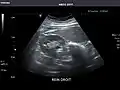

Right kidney -

Kidneys: Right and left kidneys measure 11.5 cm and 12 cm in length respectively. No hydronephrosis. Small left lower pole kidney cyst.